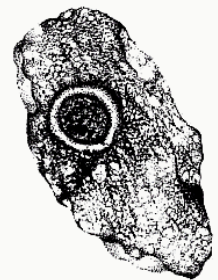

Iodamoeba butschlii (cyst)

Iodamoeba butschlii (cyst)